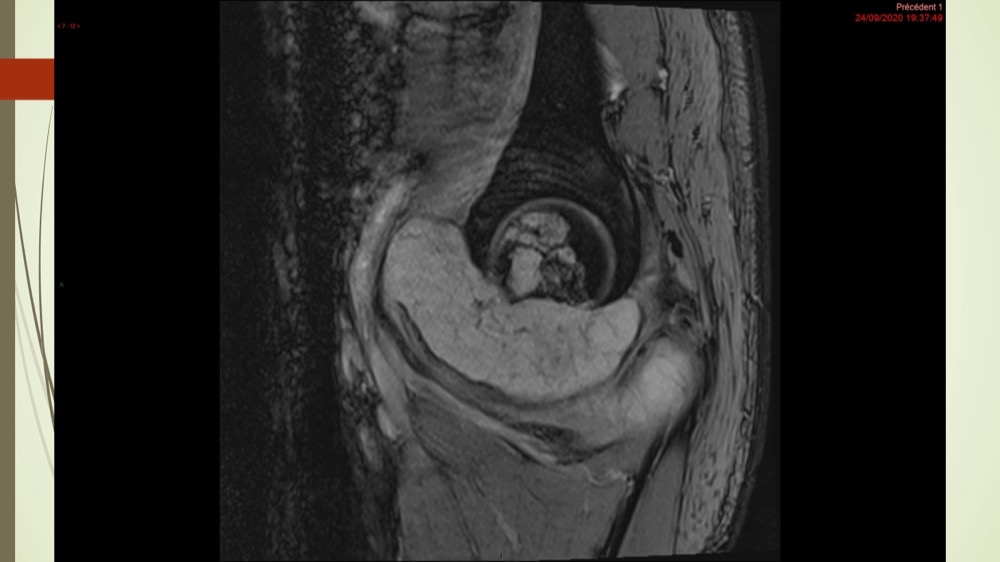

Coxalgie traînante

Kévin Mahé 29/06/2022